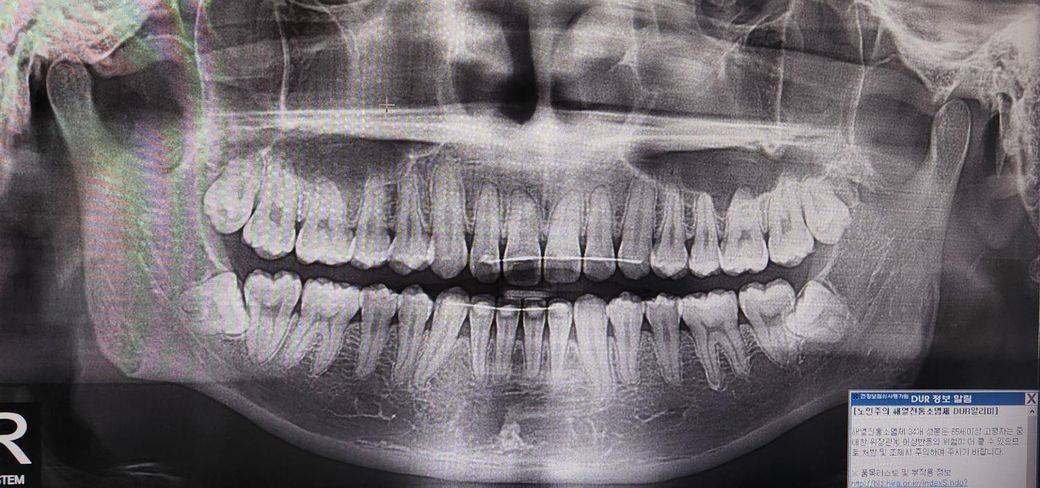

아래 매복 사랑니의 경우 신경관과 인접하고, 옆 어금니와 가깝게 붙어있어서 난이도 있는 발치입니다.

옆 어금니의 치아 뿌리를 흡수시킬 가능성도 있으나 발치 중에도 옆 어금니가 비의도적으로 손상될 수도 있습니다

옆으로 누워있는 수평매복 사랑니입니다. 그냥두면 사랑니 바로앞 어금니 상하게 하니 가능한 빨리 뽑는 것이 좋습니다.